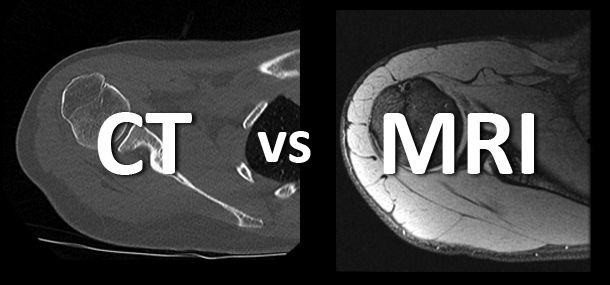

When a doctor advises an imaging test, one of the most common questions patients ask is:“Should I do an MRI...

Diagnostic imaging is a valuable aid in modern medicine towards early and correct diagnosis of disease. The best known and...